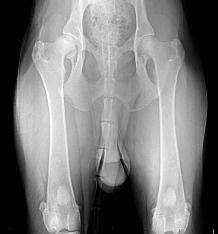

| European Import--Simon De La Madonina, IGP1 (6/28/2017) Hips FCI-HDA Elbows FCI-ED-0 DM Clear Sire--V1 Turkey & Middle East Sieger Show 2018--SG8 JKLR BSZS 2016 Gus Vom Shepherland, IPO1 Dam--SG Milan De La Madonina This impressive male is a welcome addition to our breeding program. He has an open temperament, and is a social and lovable boy. Simon has deep red pigment, substantial bone, correct conformation, a beautiful head, exceptional temperament, and medium drives. |